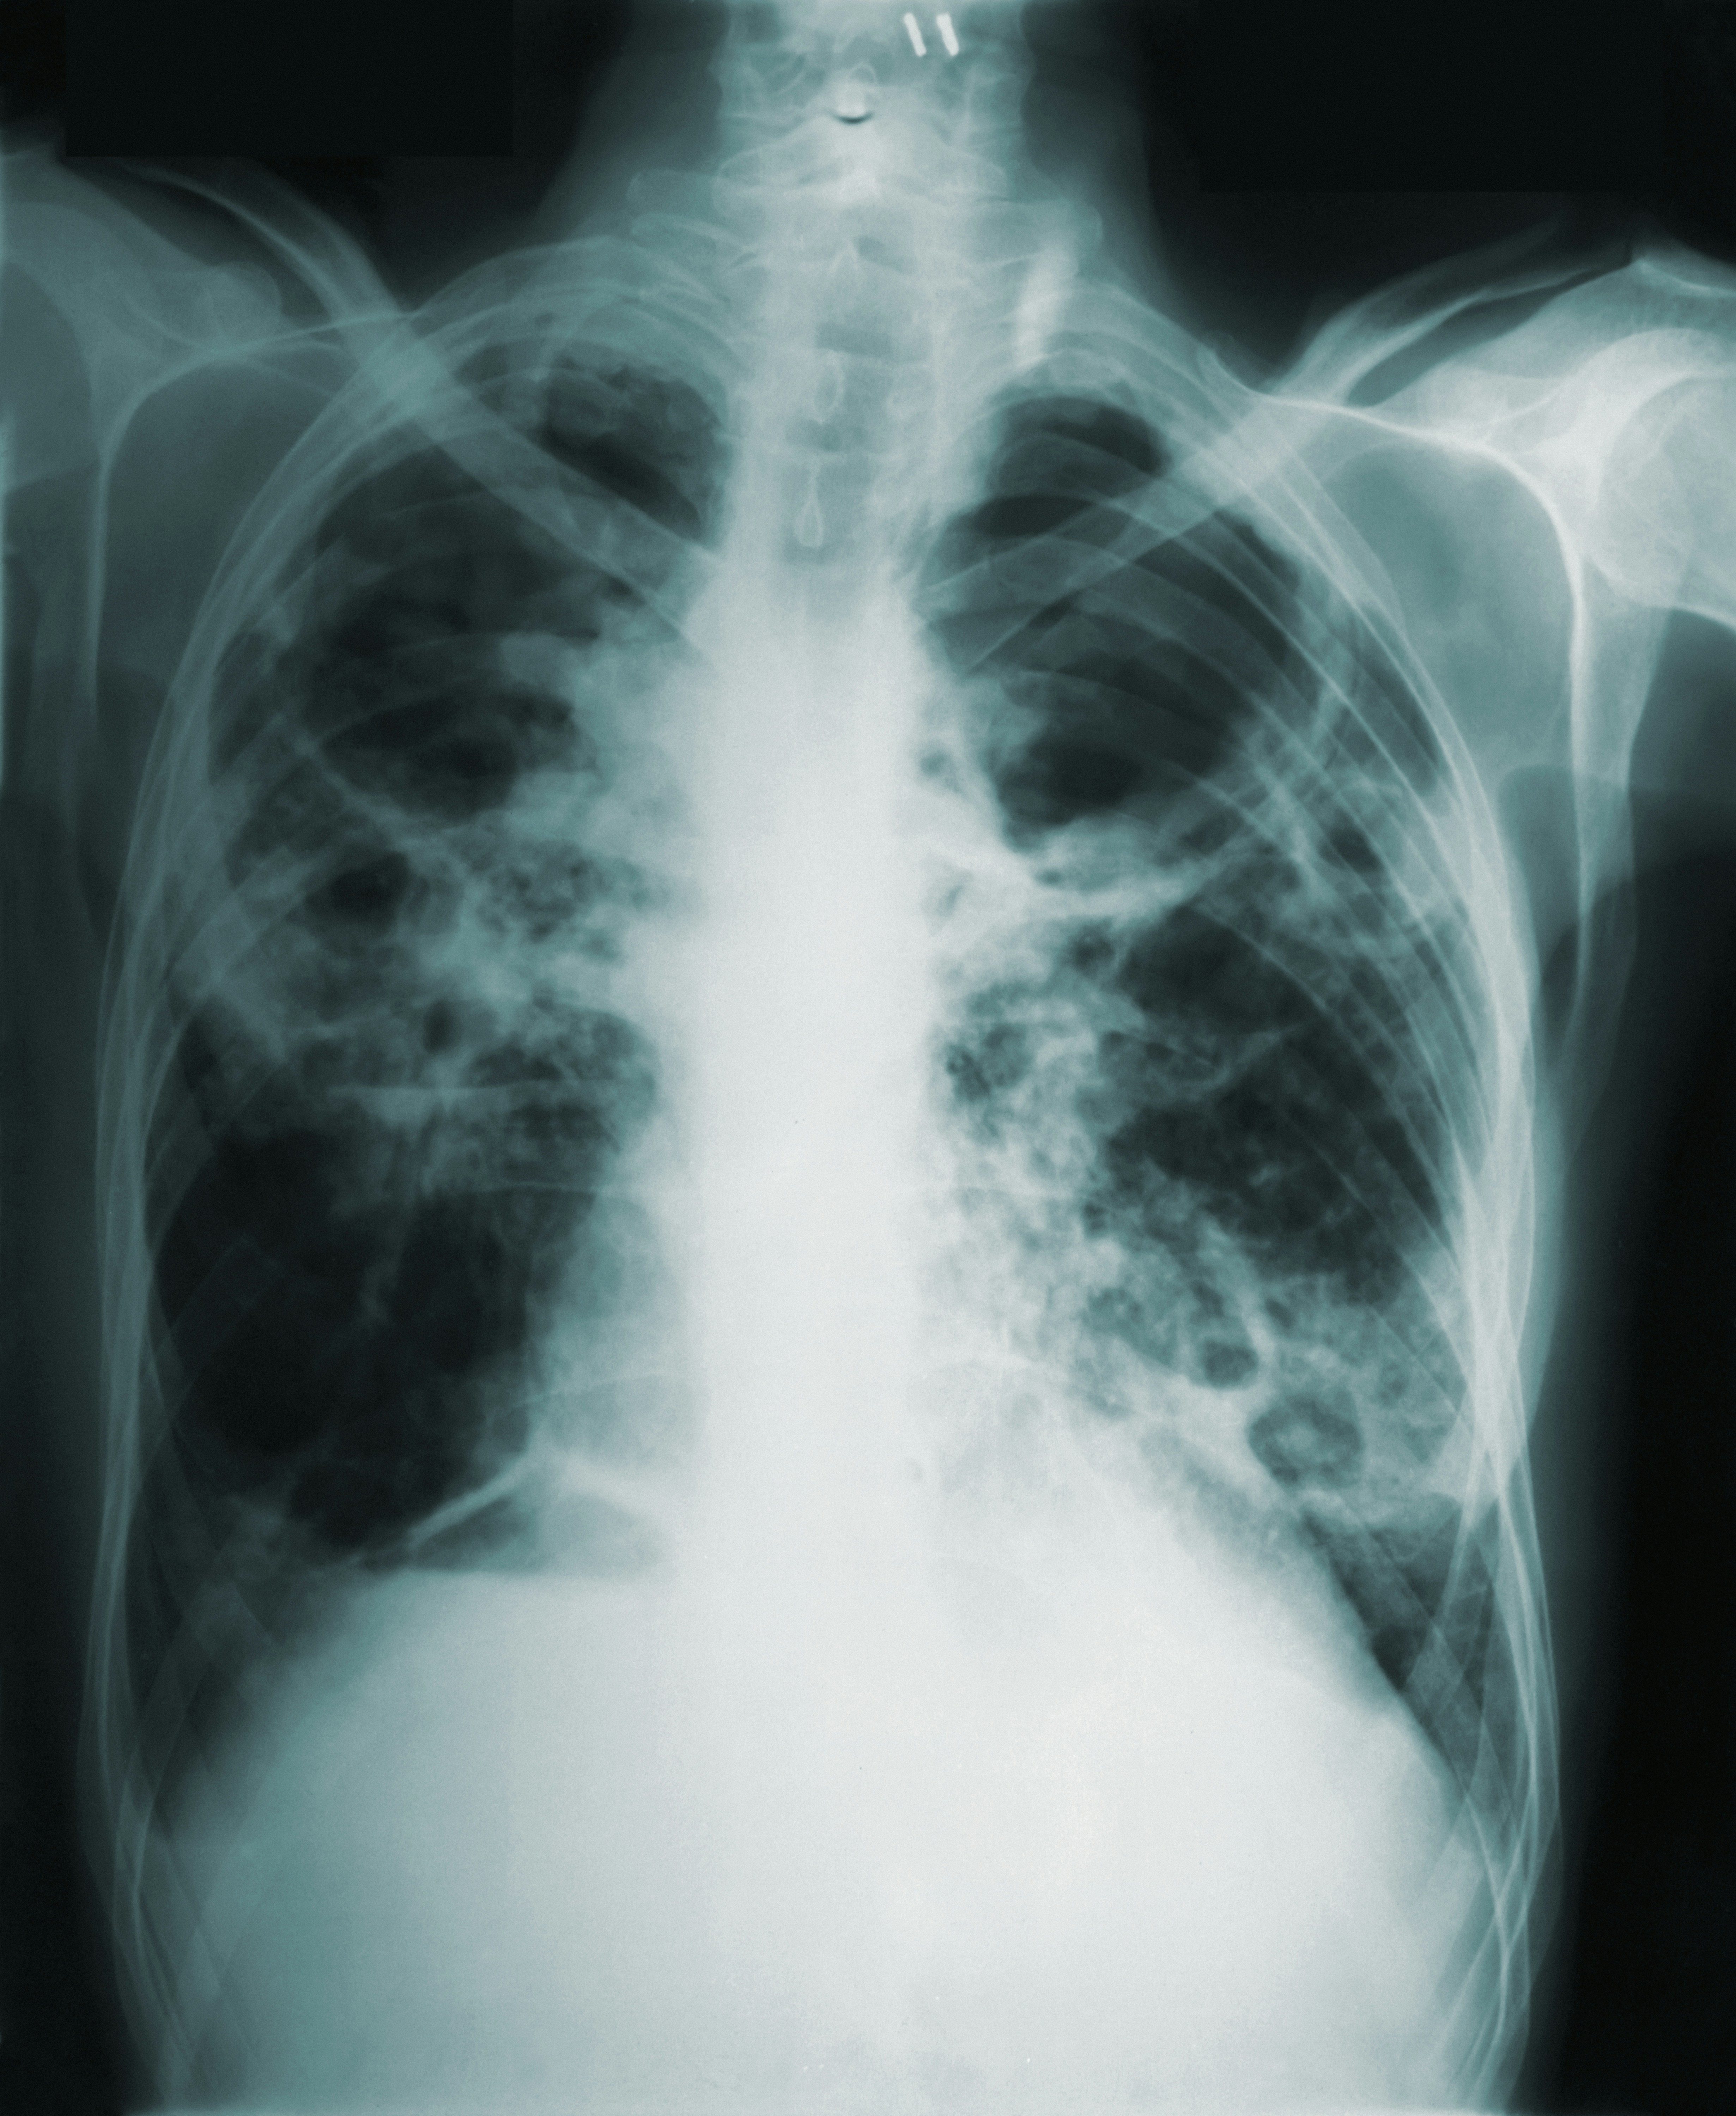

결핵 진단에는 일반적으로 병력, 신체 검사, 영상 검사(흉부 X선 등), 실험실 검사(스푸텀 분석 및 투베르쿨린 피부 검사 등)가 결합됩니다. 결핵 치료는 일반적으로 박테리아를 죽이고 항생제 내성 균주의 발달을 막기위해 몇 달 동안 복용하는 항생제의 조합으로 구성됩니다. 결핵 진단을 받은 개인은 성공적인 박테리아 박멸과 감염의재발을 방지하기 위해 의료 기관의 규정에 따라 전체 치료 과정을 완료하는 것이 필수적입니다. 또한 활동성 결핵 환자의 밀접 접촉자에 대해 잠복 결핵 감염여부를 검사하고 필요한 경우 예방적 치료를 제공할 수 있습니다.